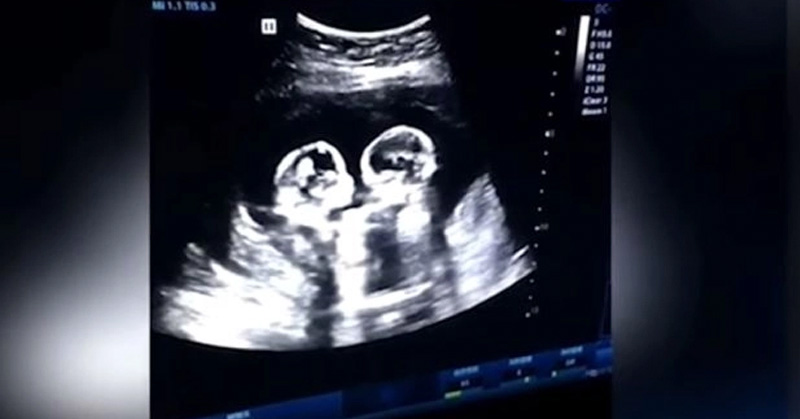

Graban pelea épica de gemelas en el útero de su madre

Las bebés compartieron la bolsa y lograron sobrevivir a pesar de las estadísticas.